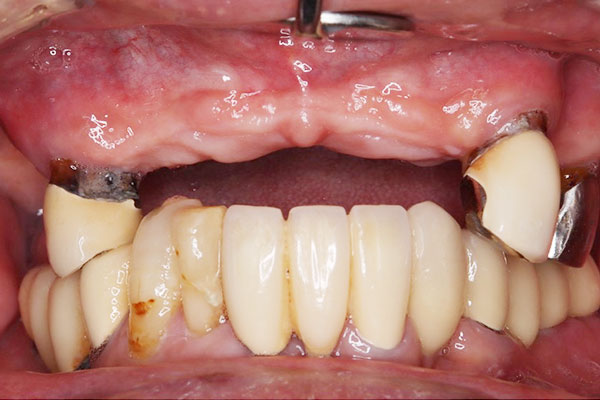

• 治療前

• 治療後

上顎6本、下顎3本。¥4,724,500

上顎は総義歯、下顎は部分義歯を使用されていた患者に対し、上顎に6本、下顎に3本のインプラントを埋入し、伵合を回復した。